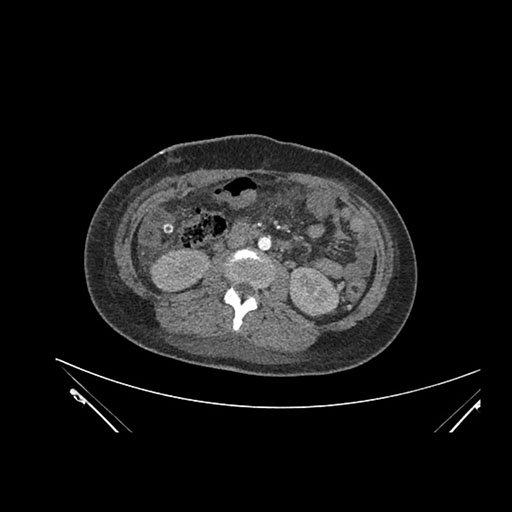

Imaging Analysis

Look through the patient's CT scan to identify any areas of concern for the necessary procedure.

Axial Venous

Based on initial findings, which issue(s) would you be most concerned about?